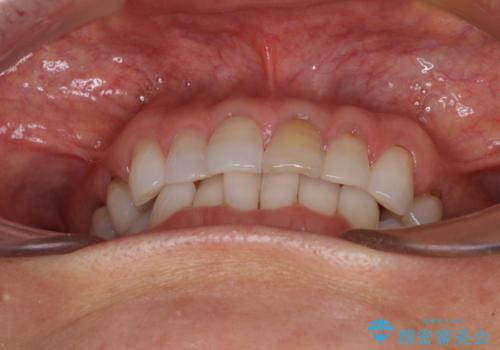

矯正治療の後戻り インビザライン・ライトでの再矯正

- 上下前歯を中心に、以前行った矯正治療の後戻りが気になるとのことで来院された患者様です。

後戻りは軽度であったため、インビザライン・ライトにて治療を行うこととしました。

矯正治療後は、再度後戻りすることを極力回避するために、下顎前歯の舌側を細いワイヤーを用いて保定することとしました。